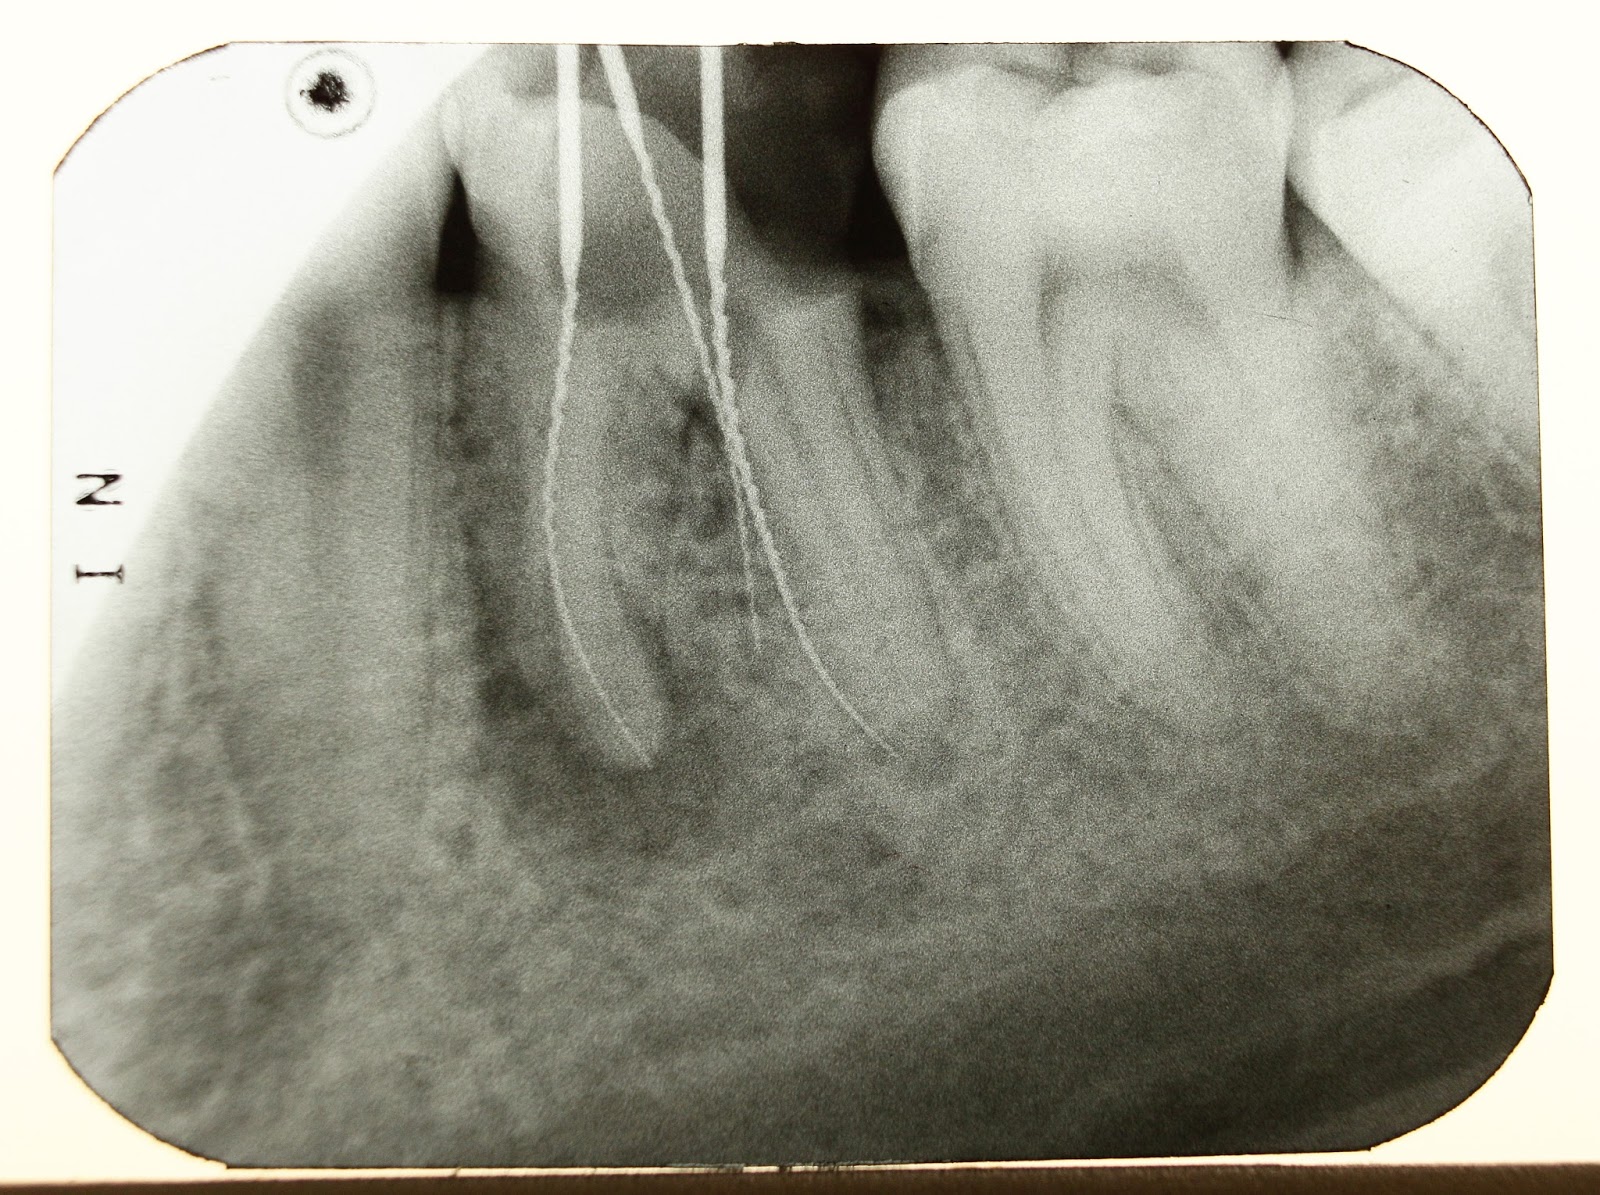

- Determinar la necesidad de estudios de imagen (radiografías, resonancia magnética, ultrasonido).

Dependiendo de los hallazgos, puede solicitar estudios de imagen para confirmar el diagnóstico. La combinación de exploración clínica y pruebas complementarias permite al traumatólogo de rodilla definir el origen del dolor y explicar al paciente las alternativas de tratamiento.